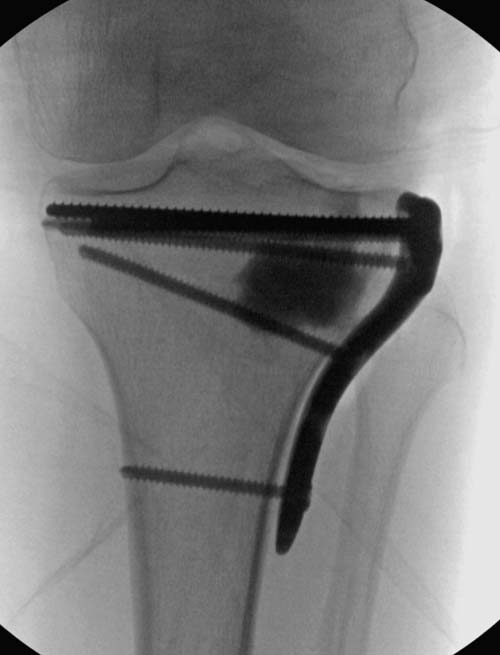

Устранение импрессии, костная аутопластика, остеосинтез опорной пластиной

задний кортекс не повреждён. Подойдёт рафтинговая пластина.

Учитывая, что у пациента молодой возраст(судя по рентгенограммам,абсолютно показано восстановление суставной линии: подменисковый доступ,подъём импренированной части мыщелка, костная аутопластика, остеосинтез, решение вопроса с мениском (шов либо парциальная резекция)).

Как подсказывают, можно с противоположной стороны приподнять сустав и заполнить костный дефект. Параллельные винты создадут достаточную опору, но иногда buttress plate за счет диафиза создает дополнительную стабильность. Структуральный материал для профилактики от раннего коллапса, и пластическим материалом служит более твердый синтетический материал (Osteoset DBM) или аутокость.